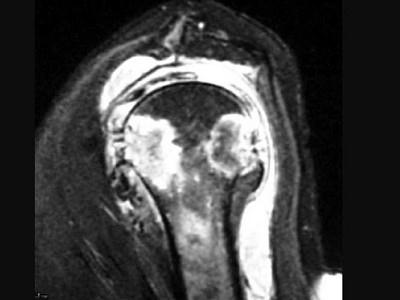

问题 女,71岁,左肩痛,系统性红斑狼疮服用高剂量的类固醇半年,结合图像,最可能的诊断是?(?)

选项 A.化脓性关节炎 B.类风湿关节炎 C.骨纤维肉瘤 D.肱骨头缺血坏死 E.肩关节结核

答案 E